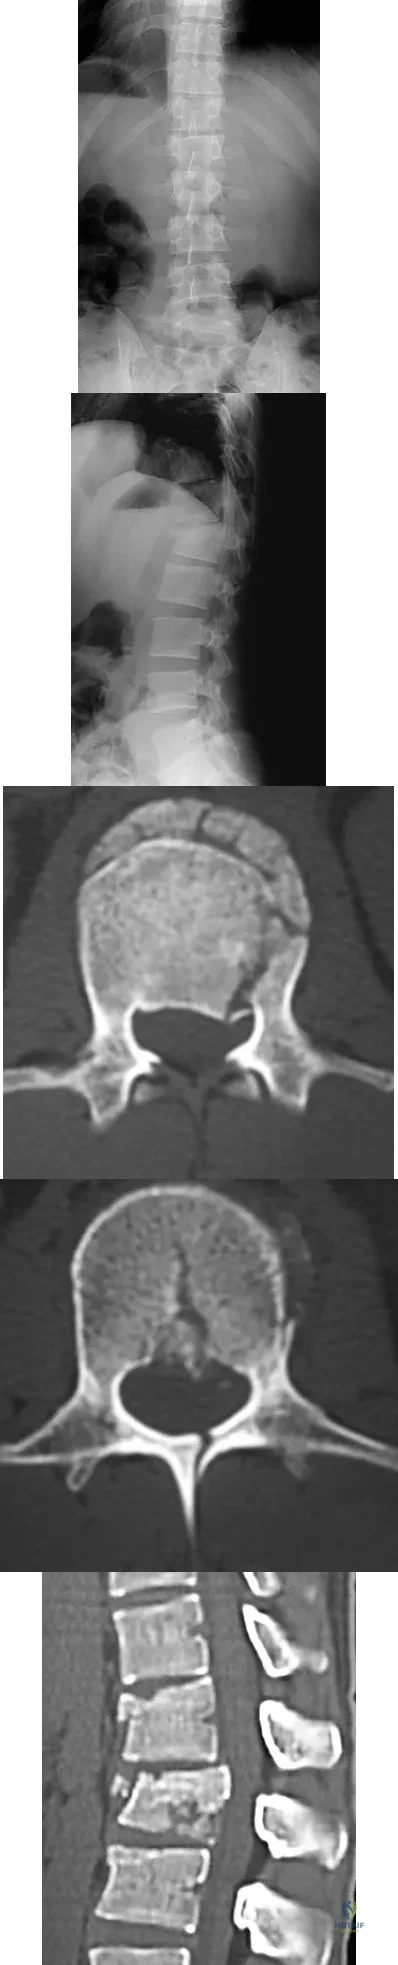

An otherwise healthy 54-year-old man who underwent a successful multilevel lumbar decompression and fusion 4 years ago now reports increasingly severe bilateral thigh claudication with paresthesia and severe back pain for the past 12 months. Physical therapy, bracing, and epidural steroids have failed to provide relief. A radiograph and MRI scans are shown in Figures 15a through 15c. He is afebrile, and laboratory studies show an erythrocyte sedimentation rate of 5 mm/h and a normal WBC count. What is the best course of action?